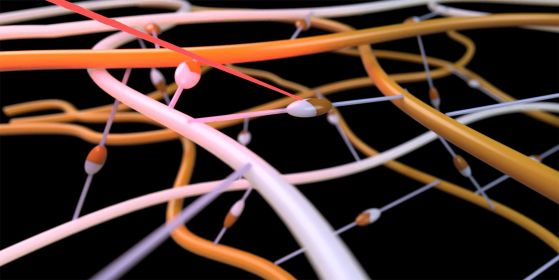

Когато лазерът (червен лъч) удари молекулата на омрежващия агент (белезникава), той се свързва с околните полимерни нишки (оранжева). Кредит: Sven Gautschi/ETH ZurichКогато лазерът (червен лъч) удари молекулата на омрежващия агент (белезникава), той се свързва с околните полимерни нишки (оранжева). Кредит: Sven Gautschi/ETH Zurich